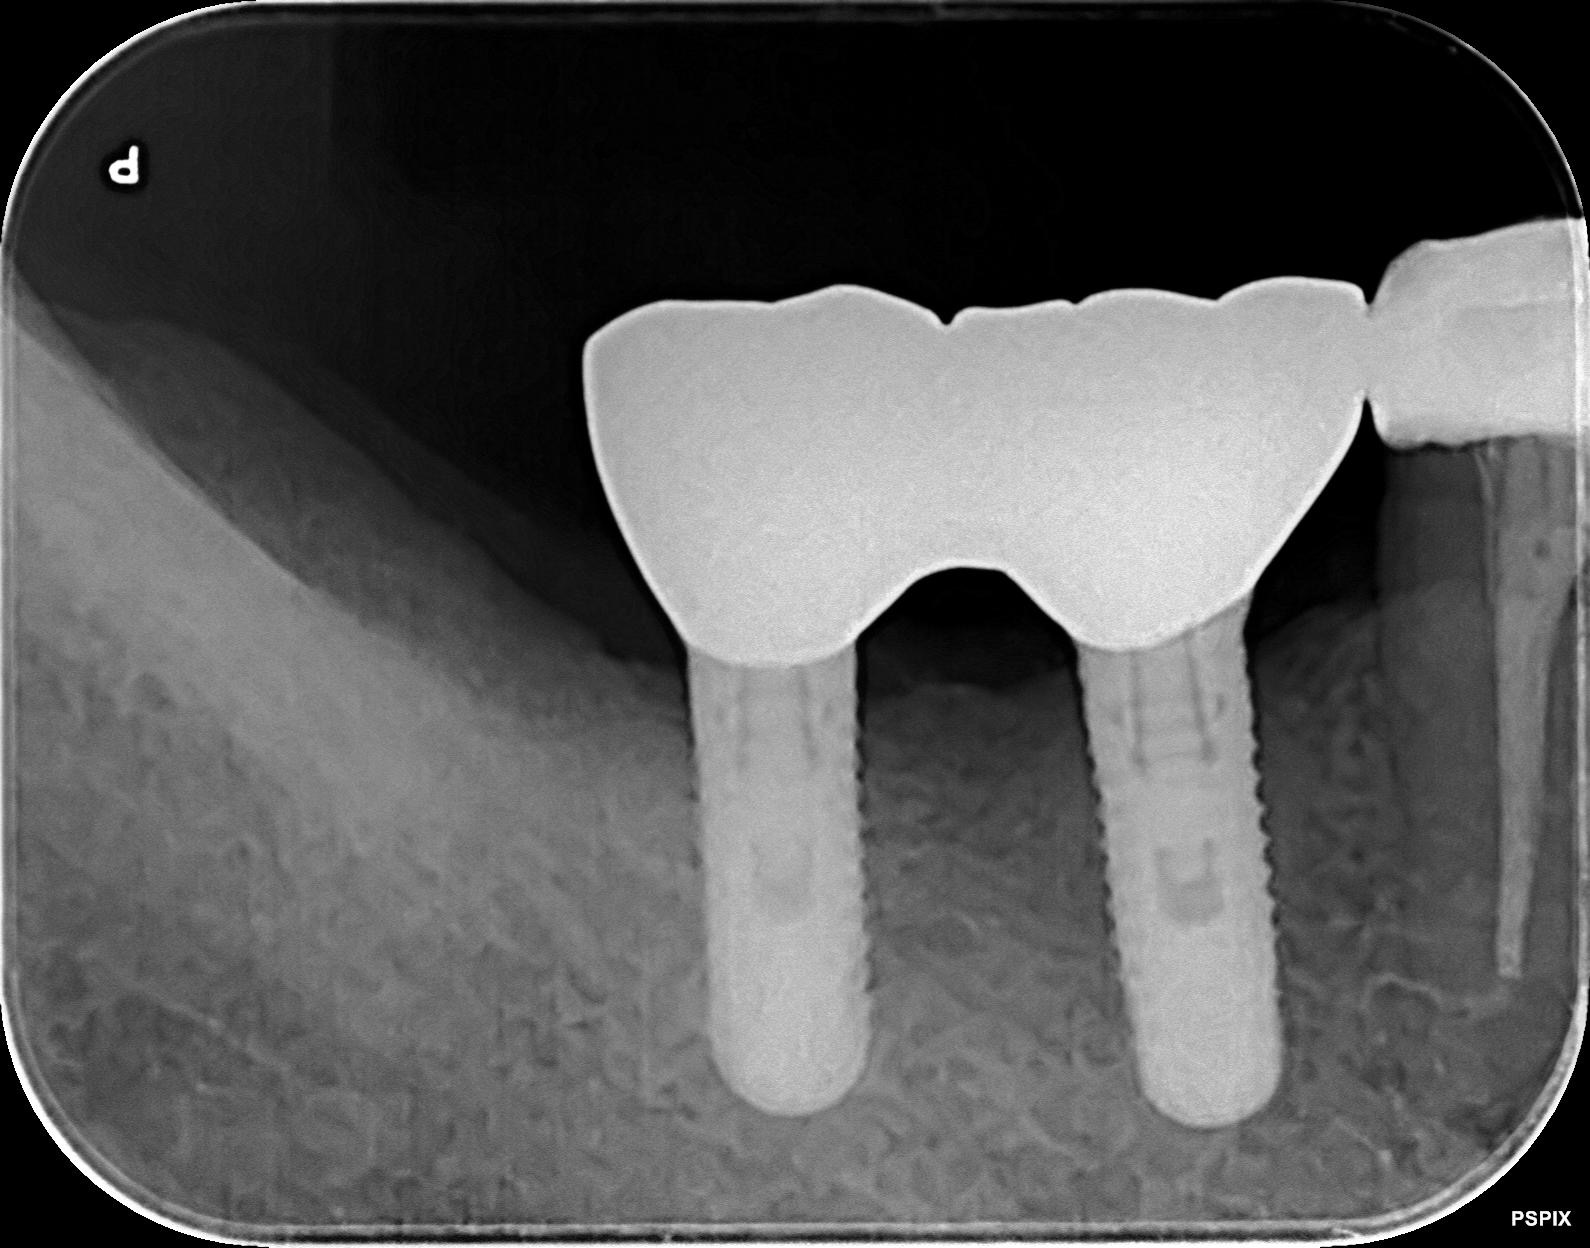

治療後

治療後のレントゲン

長期経過後

インプラントを撤去せずに再生治療を行い、長期間が経過しても良好な状態を維持しています。

現在

現在の健康な状態のレントゲン

現在の健康な状態

治療から6年以上が経過した現在も、全く問題なく健康な状態を維持しています。